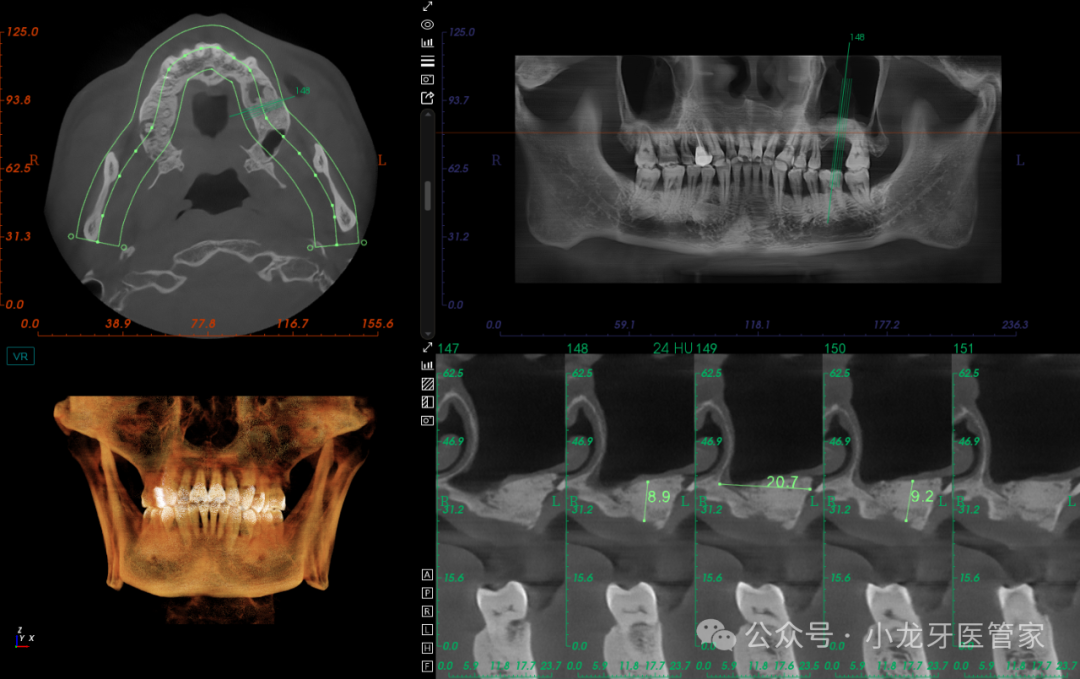

辅助检查:CBCT示左上颌窦较为宽大,窦底剩余骨高度约2mm,窦黏膜厚度约1.5mm,窦腔未见液平面,上颌窦外侧壁骨板完整。

术后当天影像学图片

(CT上看,因整体窦腔空间较为宽大,0.75g骨粉的植入面积稍欠)